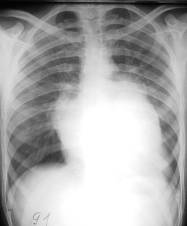

STENOZA MITRALĂ

- micsorarea butonului aortic - datorita reducerii debitului sanguin în aorta, a rotatiei cordului spre stânga si dilatarii arterei pulmonare

- rectitudinea sau bombarea arcului mijlociu - dilatarea arterei pulmonare

- micsorarea arcului inferior stâng

- dilatarea AS Prin examinarea esofagului cu pasta baritata se poate aprecia mai bine aceasta micsorare în grade variabile a spatiului retrocardiac (gradul I - amprenta a atriului pe conturul anterior al esofagului; gradul II - împingerea esofagului pâna la coloana vertebrala; gradul III - esofagul este împins posterior, dincolo de fata anterioara a corpilor vertebrali). Uneori atriul stâng apare în interiorul siluetei cardiace constituind conturul dublu concentric.

- hiluri de staza

- modificari în parenchim: transudatele alveolare determina aparitia de opacittati cu localizare mediopulmonara si bazala de intensitate slaba.